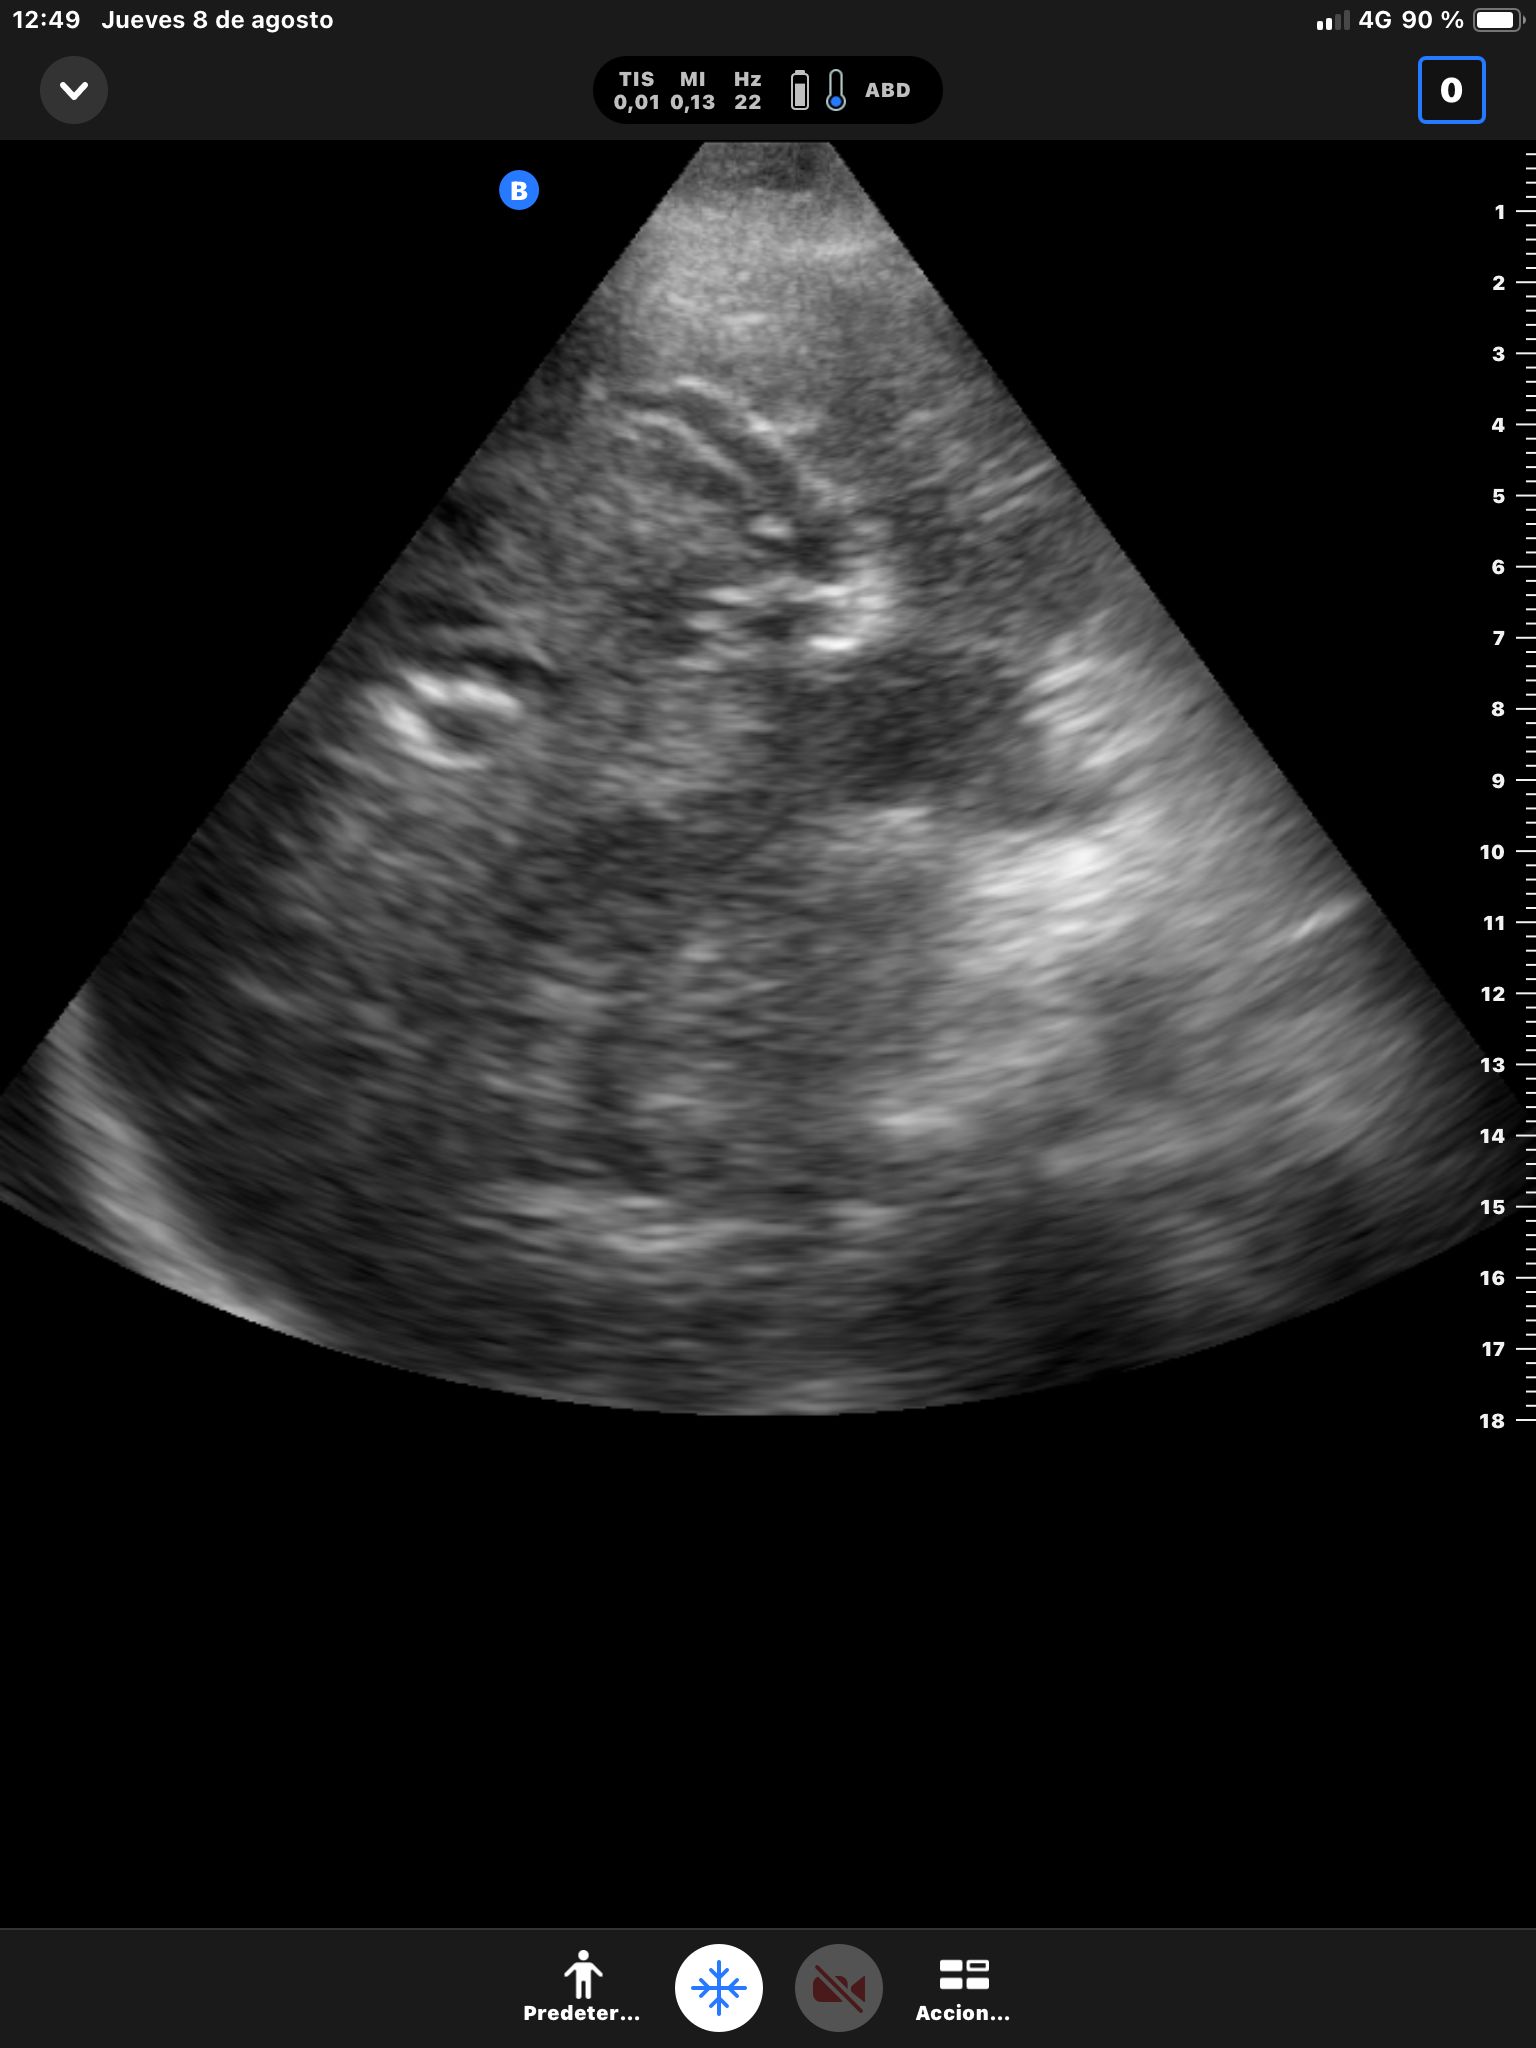

Hígado sin LOEs. Vesícula biliar con hidrops (58 mm), dilatación del colédoco (10 mm). Páncreas hiperecogénico, atrófico, Wirsung de 76 mm.

Dilatación de la vía biliar intrahepática con colédoco dilatado y atrapado por un área hipocaptante sobre la cabeza del páncreas. Atrofia del páncreas con dilatación del conducto de Wirsung que presenta calibres de hasta 8 mm con afilamiento o en el área de la cabeza pancreática.